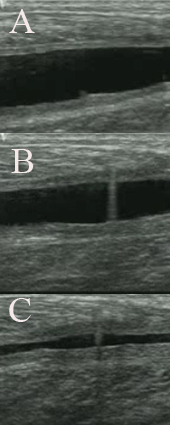

Se realiza la extracción de sangre al paciente, 20-40 cc de sangre, dependiendo de la magnitud de la lesión. En caso de presentar hematoma éste se evacua y a continuación, sin retirar la aguja, se infiltra plasma activado, PRGF®-Endoret®, adaptando el volumen a infiltrar al tamaño de la lesión. En la figura derecha se observa una imagen ecográfica representativa de un hematoma muscular (A), la punción (B) y la evacuación de dicho hematoma (C).